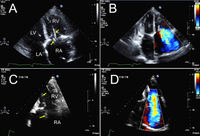

Two patients referred for severe tricuspid regurgitation after pacemaker implantation. A, C. Apical 4 chamber views (Mayo Clinic display format with right ventricle on the right) showing impingement of tricuspid leaflets by pacemaker leads (arrows). Note presence of two right ventricular leads in the first patient (panel A; one active, one abandoned lead). B, D. Corresponding Colour Doppler images demonstrating severe tricuspid regurgitation due to lead impingement.

From the collection of Sorin V. Pislaru, Mayo Clinic